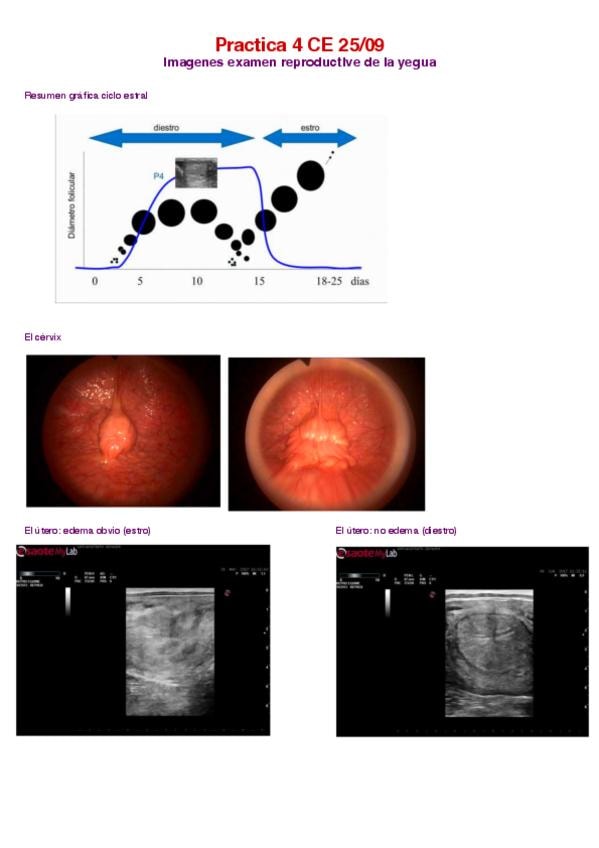

He publicado nuevos apuntes de 3º Clínica Equina I: 4.-El-ciclo-reproductivo-de-la-yegua.pdf